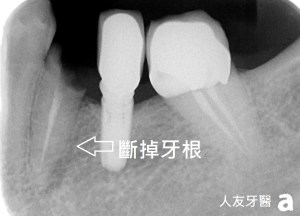

這位患者當時來就診時是因左下第一大臼齒會痛,而且已經抽過神經並且戴上假牙套了,而醫師評估完建議拔除,已告知牙根病變較嚴重,拔掉後建議再搭配植牙的方式重建。因患者有戽斗的問題,又想要同時進行植牙與矯正的治療。後來評估完建議需要拔除的牙有左下第一大臼齒和右下第二大臼齒,因都有牙根病變,醫師建議先拔除較不健康的牙齒可讓下顎牙有退後的空間。

下面兩張X-RAY 可以看到圈起來地方有黑黑的病變